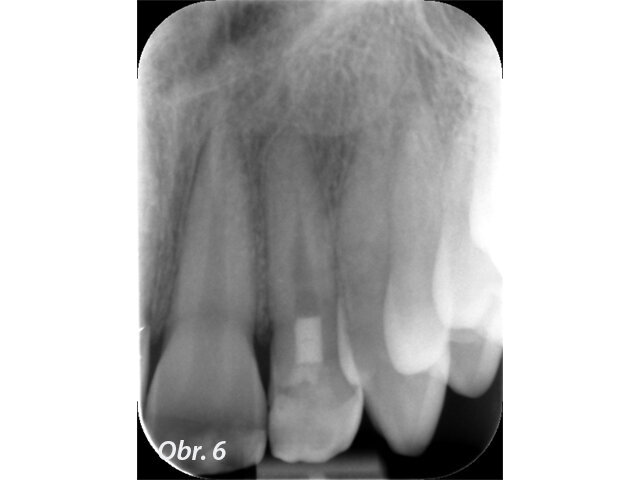

U pacienta v 10 letech byla pro úrazovou ztrátu vitality provedena revaskularizace na zubu 22. Po 2týdenní aplikaci kombinace antibiotik do prostoru pouze chemicky dekontaminovaného kořene byl po vyvolání krvácení aplikován prostředek PRGF a kořen uzavřen pomocí MTA. Zub byl rekonstruován kompozitem. Na kontrole po 5 letech je viditelně zvětšený objem tkáně kořene a absence projasnění. (Obr. 4–6)

Častou komplikací (téměř inherentní součástí) tohoto ošetření je zbarvení korunek ošetřených zubů, které je následně po vytvoření kořenové tkáně nutno řešit vnitřním bělením (obr. 7).